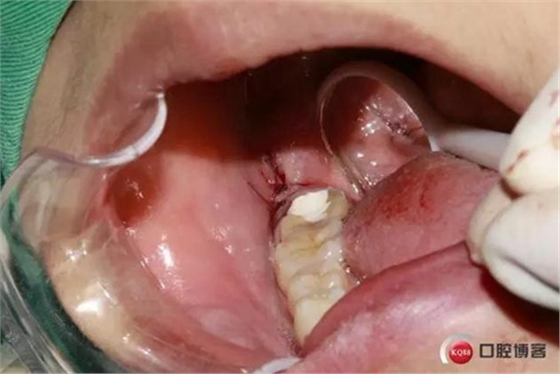

拔牙創(chuàng)口,清理周邊肉芽,切忌,不能搔刮。

縫合。

檢查。